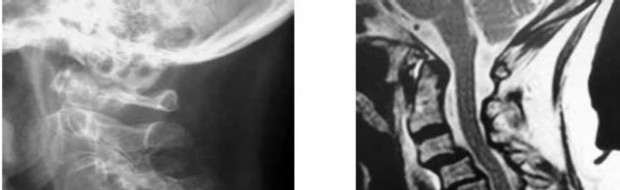

A 60-year-old male of East Asian descent presents with progressive clumsiness in his hands and an unsteady gait.

Lateral cervical radiographs reveal a continuous, dense radiopaque stripe immediately posterior to the vertebral bodies from C3 to C6. What is the most likely diagnosis?

Explanation

A 60-year-old Japanese male presents with progressive clumsiness of his hands, difficulty walking, and hyperreflexia in both upper and lower extremities. Lateral cervical radiograph reveals dense ossification extending vertically along the posterior aspect of the C3 to C6 vertebral bodies. Which surgical approach is generally preferred if the canal occupying ratio is 60% and cervical alignment is lordotic?